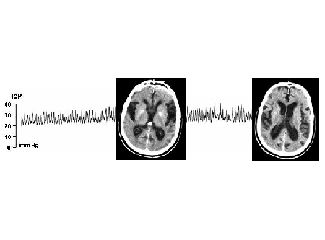

De fet, ambdues emocions estan presents en alguns trastorns psicològics. Per això, psiquiatres de l'UAB estudien les nostres respostes fisiològiques a estímuls negatius provocats. Aquesta observació podria determinar perquè certes persones són més propenses a sofrir...